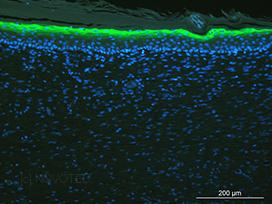

Novotec développe aussi des programmes de recherche en ingénierie tissulaire cutanée en collaboration avec des entreprises françaises et étrangères : caractérisation de substituts cutanés dermiques, épidermiques et dermo-épidermiques, implantations des substituts cutanés chez la souris nude (habilitation à la chirurgie sur les petits animaux, mise en place d'un consortium avec plusieurs entreprises et animaleries pour la prise en charge d'un projet pré-clinique complet) et analyse des prélèvements au cours d'études précliniques. La maîtrise des différentes techniques d'analyse tissulaire et cellulaire a permis de réaliser des études cinétiques, de biocompatibilité et d'intégration des substituts cutanés. Les étapes clés de la réparation cutanée (néo-vascularisation, ré-épithélialisation, remodelage matriciel, ...) ont pu être décrites aussi bien d'un point de vue génique que d'un point de vue protéique. L'ensemble de ces analyses a permis de répondre à trois questions essentielles : Qui, Quand et Où ?